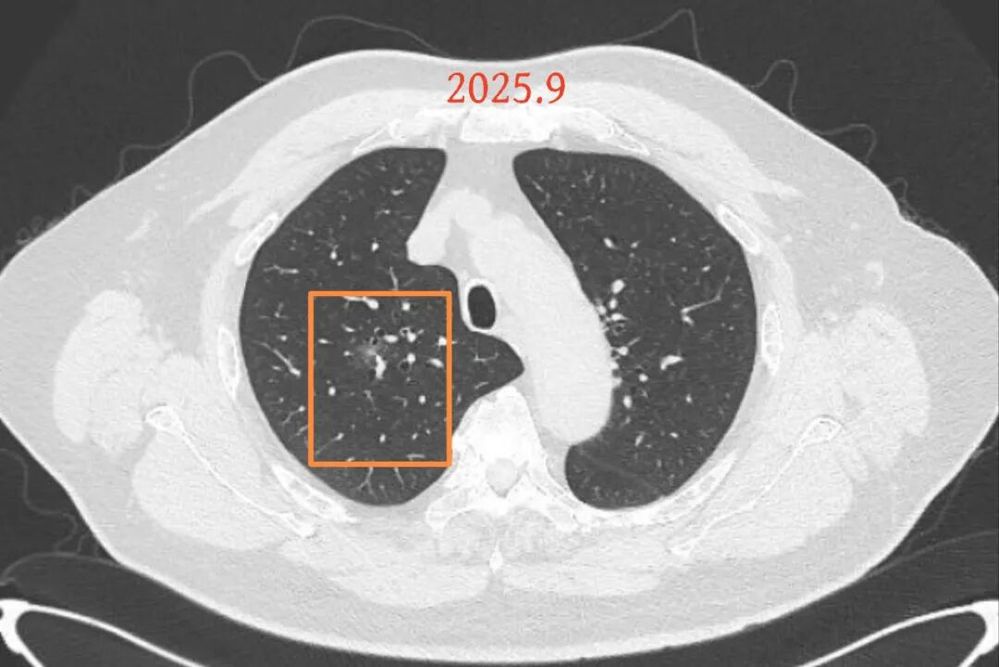

第二次问诊:2025.9

影像展示与分析:

病灶B似乎灶内有少许密度略偏高,但瘤肺边界欠清晰,总体说不上太显著的进展。

我的意见:

右肺上有两处病灶,仍然是磨玻璃密度,整体轮廓较为清楚,对比23年的说不上非常明显的进展。确实需要考虑微浸润性腺癌可能性大(上次我也说原位癌或者微浸润性腺癌)。主要纠结于位置太靠中间,如果手术基本上得切除右肺上叶。我的想法是已经75岁的年纪,如果进展很慢的话,是不是也不是一定得开刀。或者随访看它进展情况,到时候再来考虑。个人稍微倾向于仍然六到九个月复查,有进展并风险增加再手术,或者其他方法干预。意见供参考!

后续交流:

当时结友自己还觉得有点实性成分,血管感觉也有增粗。而我觉得整体密度仍是磨玻璃,轻微的变化仍不足以影响临床决策的程度。